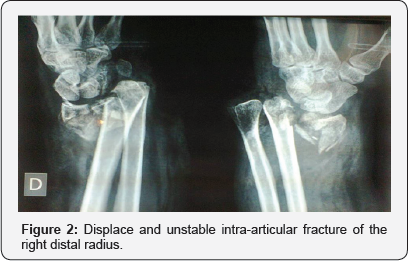

A 52-year-old woman presents to the emergency room 3 hours after a car accident, with an isolated grade 1 open fracture of the right distal radius associated with a volar-ulnar wound draining serosanguinous fluid (Figure 1). The fracture is intra- articular, notably displaced and unstable before reduction (Figure 2). The patient was initially underwent emergent operative wound irrigation, debridement, administration of intravenous antibiotics, and tetanus prophylaxis. In addition, immediate skeletal stabilization of the fracture was obtained by means an external distal radius fixator (DePuy Synthes).